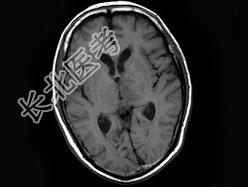

- 单项选择题男,70岁, 头痛,嗜睡伴癫痫发作2次, 行MRI平扫及增强扫描见颅内多发病灶,曾行放射治疗, 病灶明显缩小(此图为治疗前图),据此最可能的诊断为 ( )

A、颅内转移瘤

B、淋巴瘤

C、胶质瘤

D、血管瘤

E、未见异常